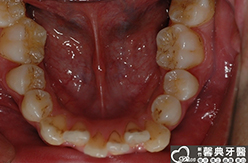

上、下顎前突,俗稱暴牙,由於上下前牙向前暴出,在外觀上容易產生牙齒外露的現象,雙唇較難自然閉合,嘴唇看也來也會比較厚。

患者︰趙同學,20多歲,學生。

主訴︰齒列不正,暴牙,不好看。

治療計劃︰上下顎齒列平整、後縮,重建正常咬合關係。